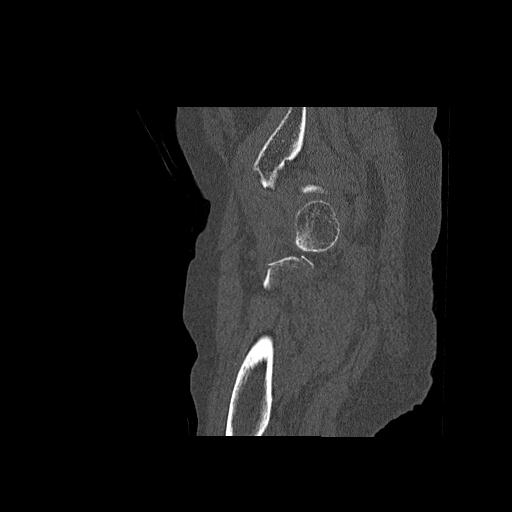

110286 2/17 股関節 2R 74歳女性 右人工骨頭

82084 1/14 1/20 股関節 2R 78歳男性 右人工骨頭

102811 1/13 股関節 2R 1/19 2R 80歳女性 右DHS